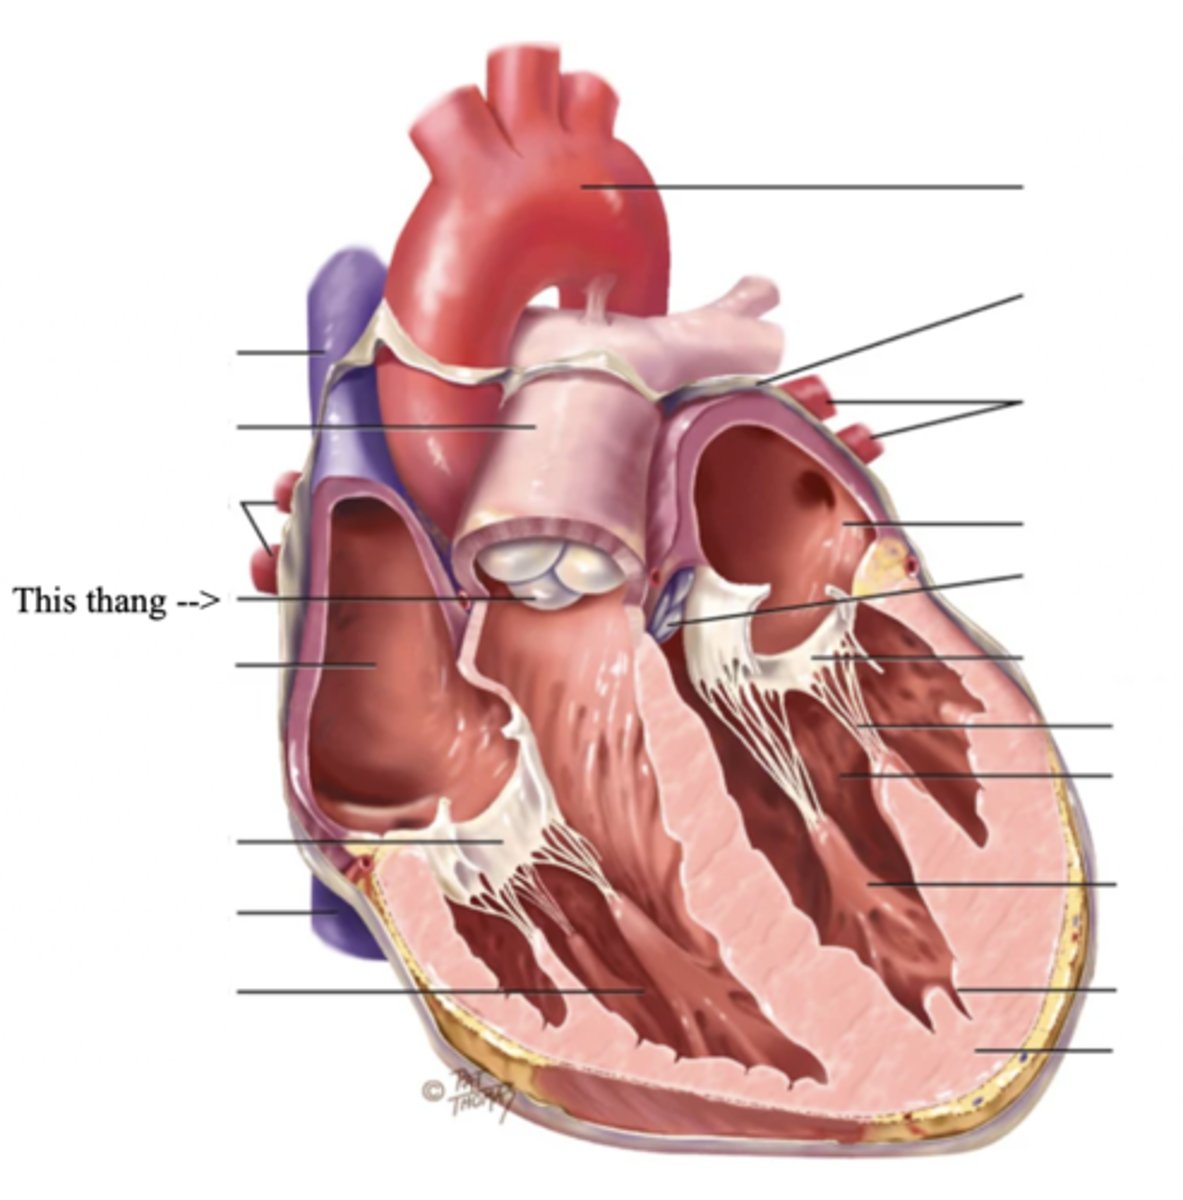

Anatomy of the Heart

2 Main Types of Valves of the Heart

- Atrioventicular

- Semilunar

Atrioventricular Valves (AV) (2)

The valves that separate the atria and the ventricles

The 2 Atrioventicular Valves of the Heart

- Tricuspid

- Mitral

Tricuspid Valve

- The right AV valve separating the right atrium from the right ventricle

- Connected by 3 chordae tendinae

Mitral (Bicuspid) Valve

- The left AV valve separating the left atrium from the left ventricle

- Connected by 2 chordae tendinae

Chordae Tendinae

Fibers (heart strings) attatched to the tricuspid and mitral valve which pull it closed when papillary muscles contract, preventing back flow of blood